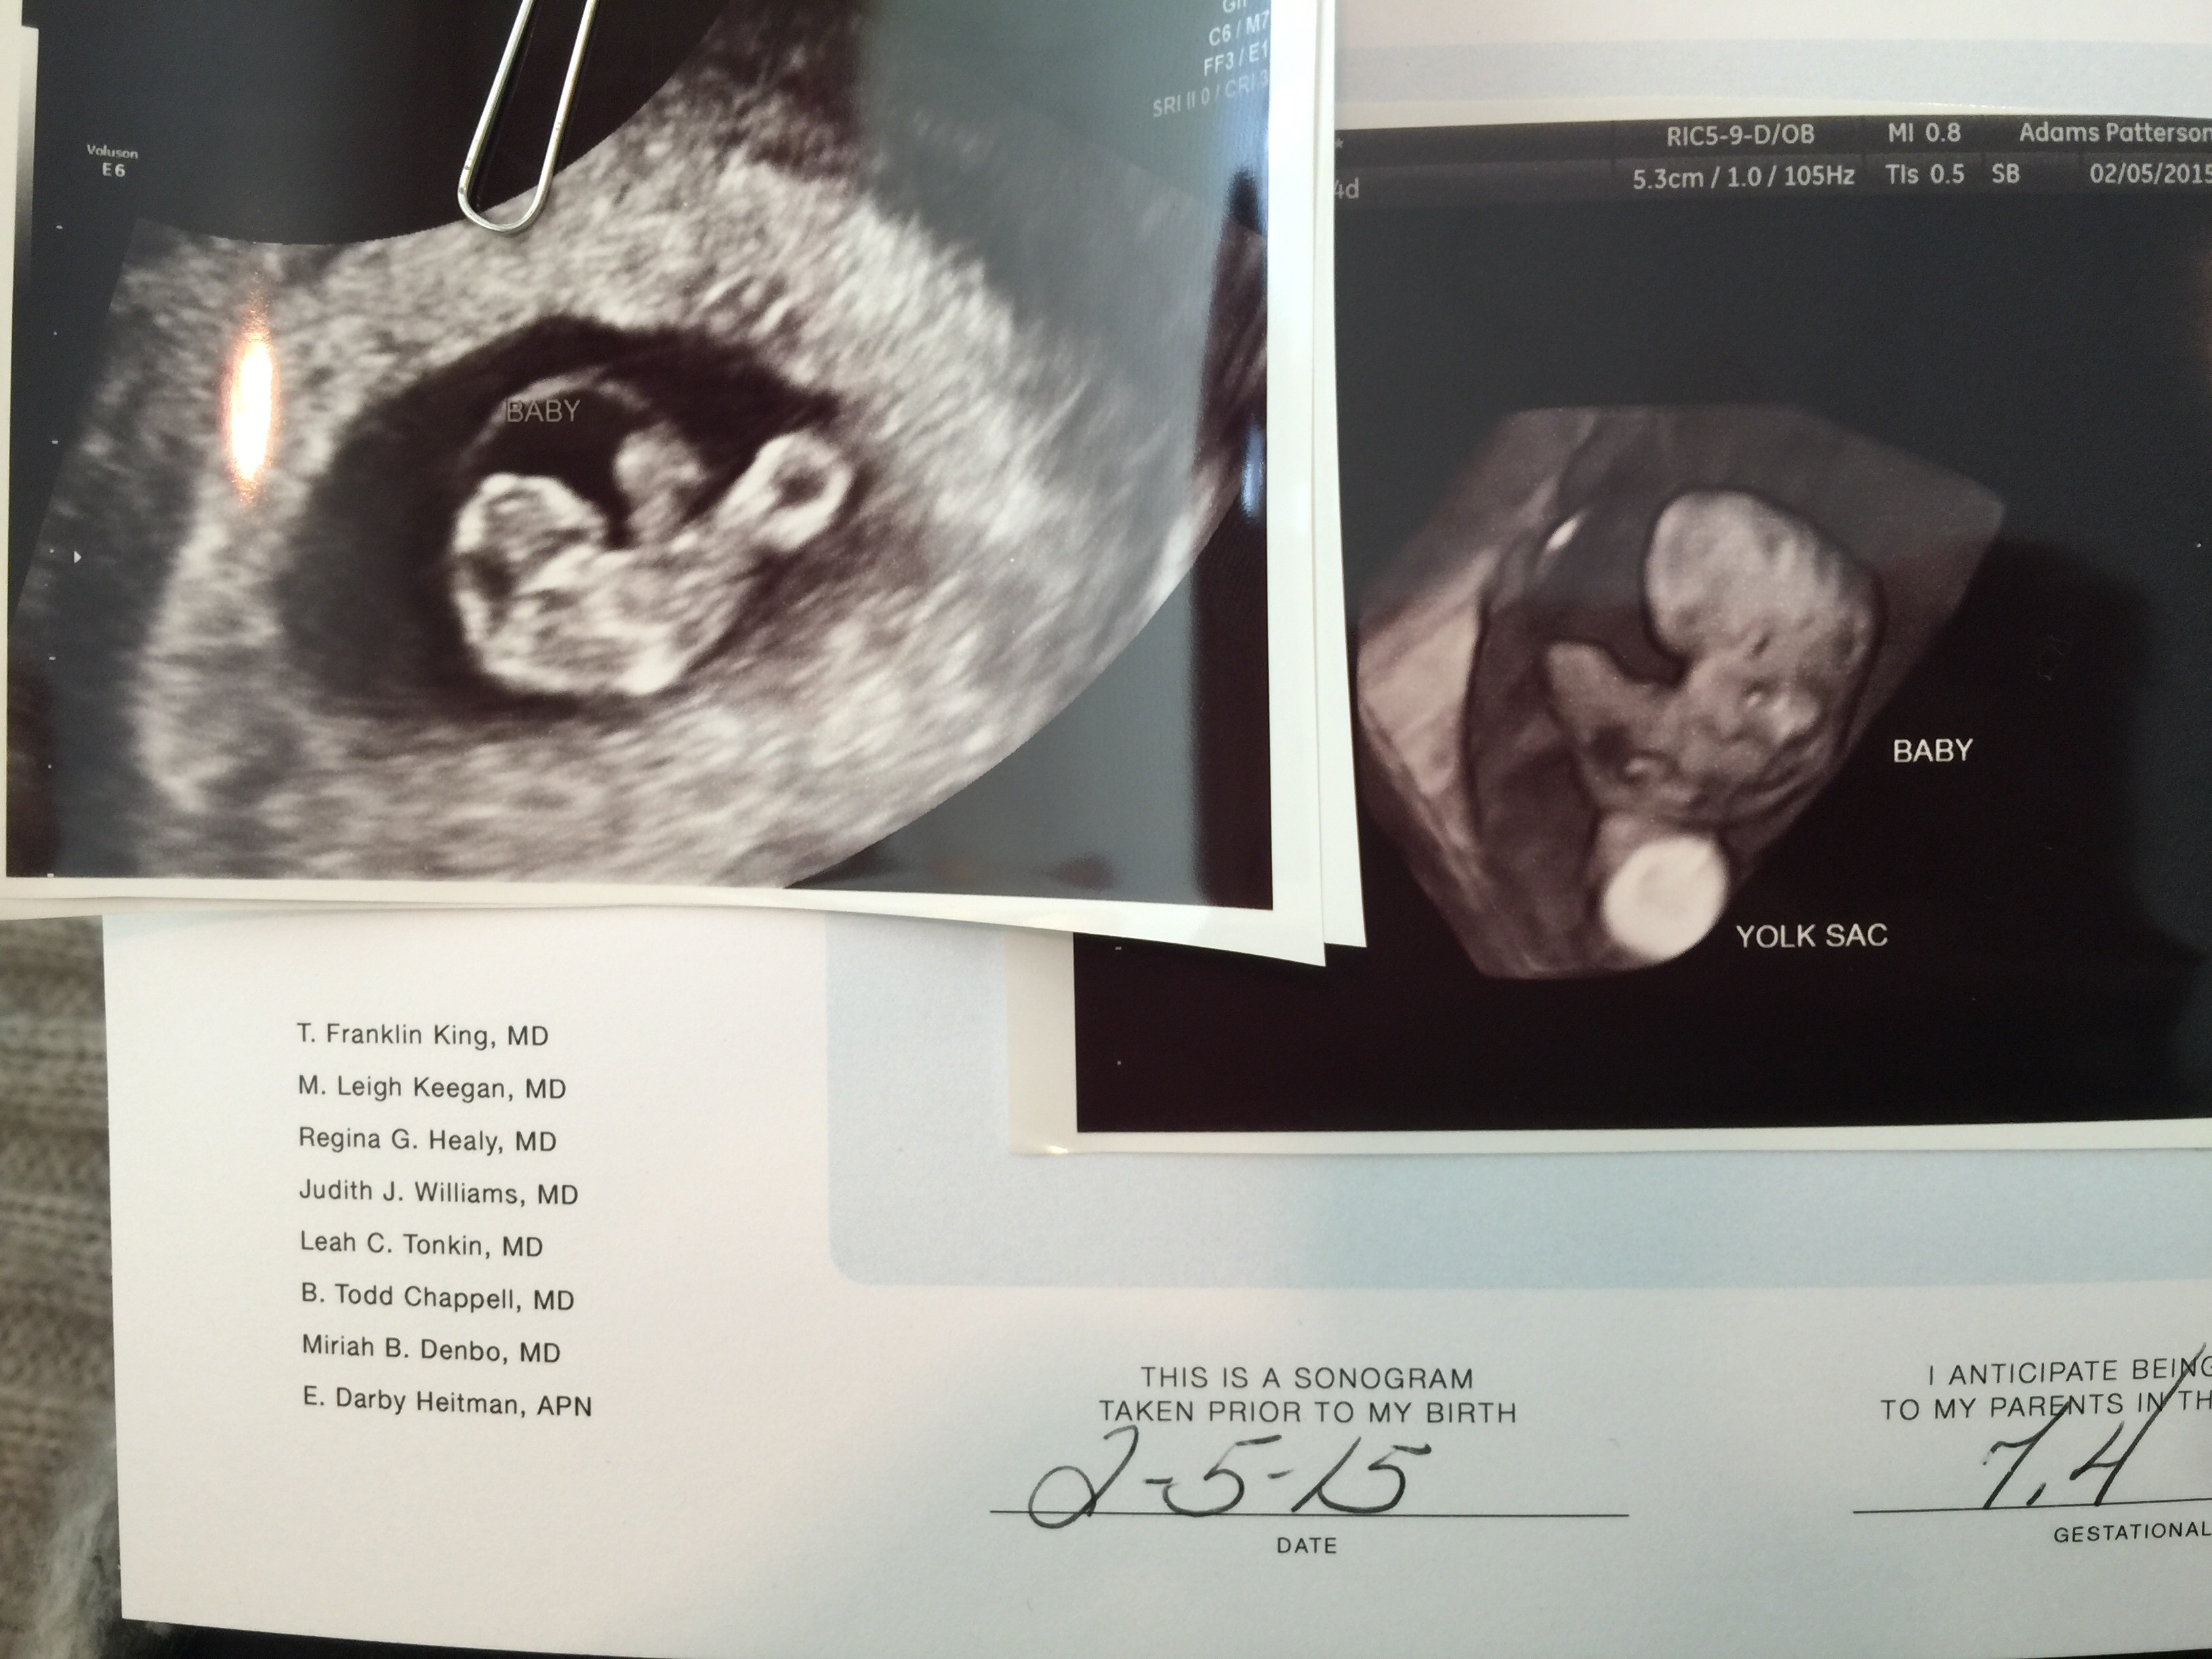

BFP: 1/22/15. EDD: 9/23/14. Rainbow baby!

Here is DS looking at his bro or sister for the first time.